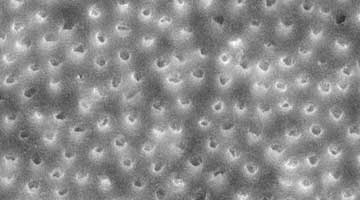

What we want in chemical irrigation is to maximize the cleansing ability of the irrigants, while minimizing their deleterious impact on the remaining dentin. Recently, new irrigation formulas have been introduced (Irritrol, Essential Dental Systems, South Hackensack, New Jersey). Irritrol is specially formulated with a proprietary blend of chelators, chlorhexidine, and additional disinfecting surfactants, which work together in synergy to maximize disinfection and open up the dentinal tubules, while also conserving the dentinal tooth structure. The proportions of each component comprising Irritrol are perfectly balanced so that effective removal of the smear layer without excessive demineralization is possible (figure 3). Dentinal erosion as a consequence of excessive demineralization exposes the underlying collagen framework of dentin, resulting in weaker tooth structure as well as negatively impacting the capacity of root canal sealants and cements from bonding as effectively. (3) The perfectly blended, active ingredients of Irritrol work together to disinfect or remove the smear layer significantly better than EDTA or chlorhexidine alone.